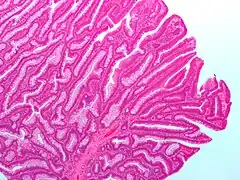

Villous adenoma

These adenomas may become malignant (cancerous). Villous adenomas have been demonstrated to contain malignant portions in about 15–25% of cases, approaching 40% in those over 4 cm in diameter.[7] Colonic resection may be required for large lesions. These can also lead to secretory diarrhea with large volume liquid stools with few formed elements. They are commonly described as secreting large amounts of mucus, resulting in hypokalaemia in patients. On endoscopy, a "cauliflower' like mass is described due to villi stretching. Being an adenoma, the mass is covered in columnar epithelial cells.